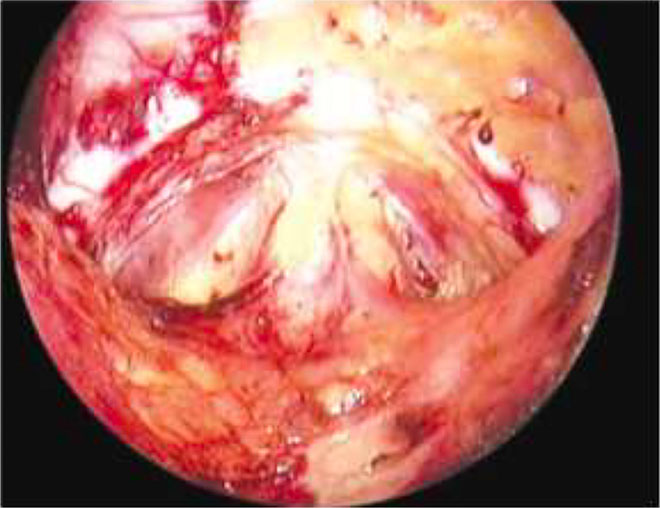

Risk of bladder injury is particularly increased in patients with a history of cesarean section. This risk can be minimized using the lateral window technique (Figure 7) in which, after dissecting the round ligament and uterovesical peritoneal fold, the laparoscopist stays above the uterine artery and adequately displaces the bladder to safely secure the artery and avoid injury.

In the correct plane, the bladder can be pushed below the cervix without needing extensive separation from the vagina, thereby reducing the risk of bleeding. In the event of a bladder injury, a two-layer closure (Figure 8) is recommended, after which the primary surgery can be continued.

7

Lateral window technique for identification of the uterine artery and ureter in a patient with previous cesarean section.